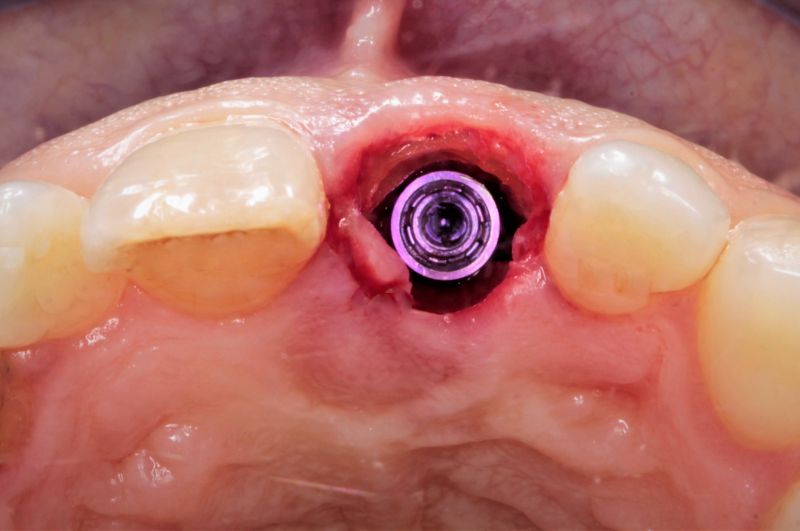

Trong 3-4 tuần đầu, Implant thường có nguy cơ lung lay vì xương cũ tiêu biến trước khi xương mới hình thành (giai đoạn nguy hiểm của Implant) bởi cơ thể có một cơ chế bảo vệ tự nhiên chống lại dị vật.

???? Tiêu xương cục bộ (Giai đoạn 2-4 tuần sau cấy ghép – “Giai đoạn nguy hiểm”)

⏳ Nhưng trong 3-4 tuần đầu, xương mới chưa kịp hình thành, còn xương cũ bị tiêu biến, khiến Implant dễ lung lay – đây là “giai đoạn nguy hiểm”.

✅ Ổn định sơ khởi tốt (Primary Stability)

Nếu Implant được cấy với lực ổn định tốt (Torque 35-45 Ncm), nó ít có nguy cơ lung lay ngay cả khi xương cũ bị tiêu biến.